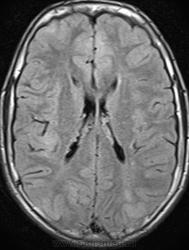

Это болезнь Бурневилля - одна из форм факоматозов?

Да, это болезнь Бурневилля-Прингла, один из видов факоматоза. Врожденное заболевание, развивается из-за нарушений в одной из хромосом.